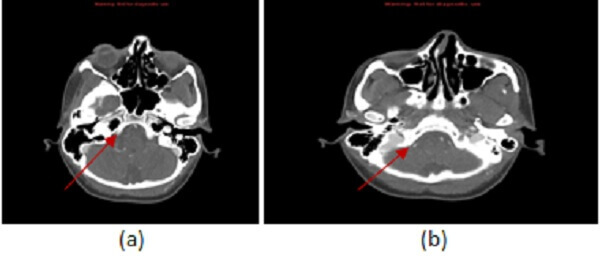

Figure 1: (a)-(c) Sequential axial images from a CT angiogram of the head and neck demonstrate an abrupt caliber change of the distal right V4 segment of the vertebral artery (red arrows) tapering in a “string” sign consistent with the diagnosis of dissection.

MRA and CTA are the most commonly used imaging modalities to evaluate for dissection. Imaging findings common to both modalities include: long segment smooth tapering of the vessel – “string sign”,   vascular occlusion (absence of contrast or signal in the vessel lumen), focal lumen caliber change

and intimal flap with a double lumen for the steno-occlusive form; eccentric dilation of the vessel with luminal contour irregularity for the aneurismal form.